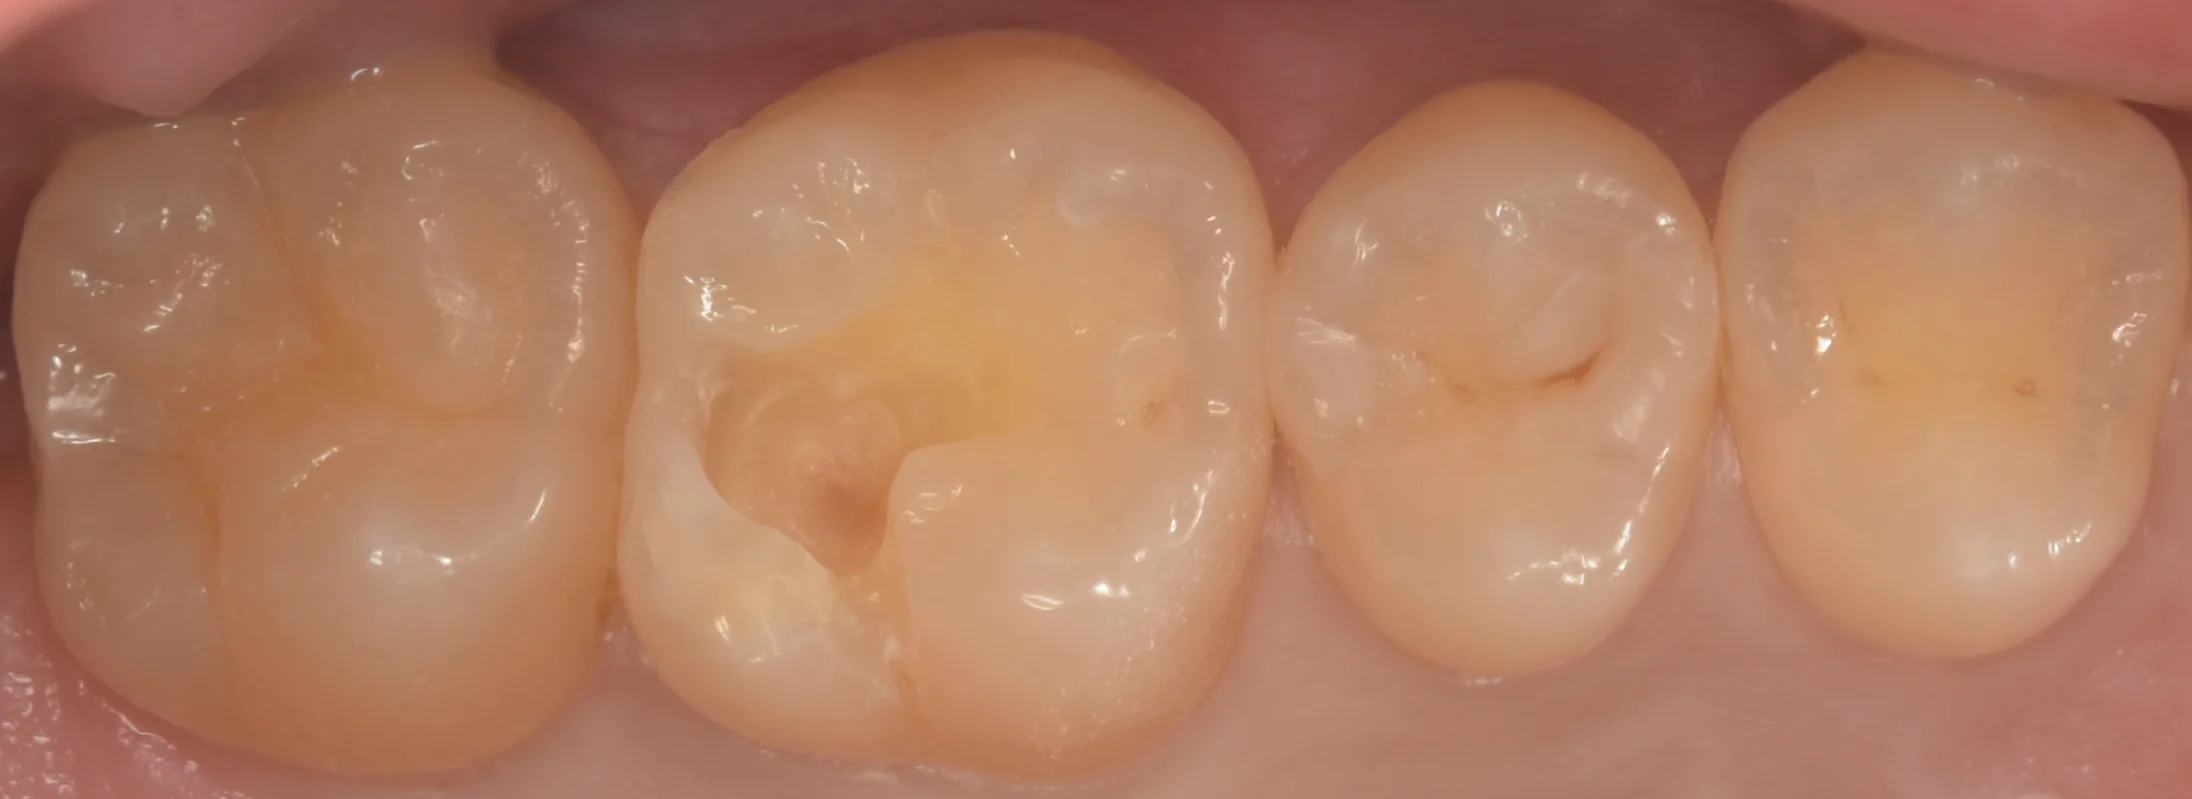

虫歯を取り切ったのがこちらになります。

本来の歯の色が出て、綺麗になっているのがわかるかと思います。

最深部に一部着色が残存していますが、ここについては虫歯ではないです。

ただし着色が残っている部分については接着力が落ちてしまうため、私は基本的にはなるべく除去するようにしています。

今回はこれ以上取ると神経へのダメージになりそうだったためそこの一部の着色のみを残しました。

そして詰め終わったのがこちらになります。

割と自然に再現できたかと思いますヽ(゚∀゚)ノ パッ☆